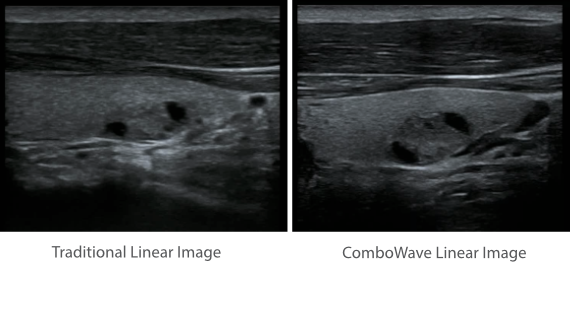

Sobre la base de un profundo conocimiento de las necesidades del cliente, el DC-60?ECHO con X-Insight estå dise?ado para brindar alta eficiencia con imågenes precisas, lo que se ve potenciado con eXpress Clarity (claridad exprés), eXceptional Intelligence (inteligencia excepcional) y eXceeding Experience (experiencia extraordinaria).